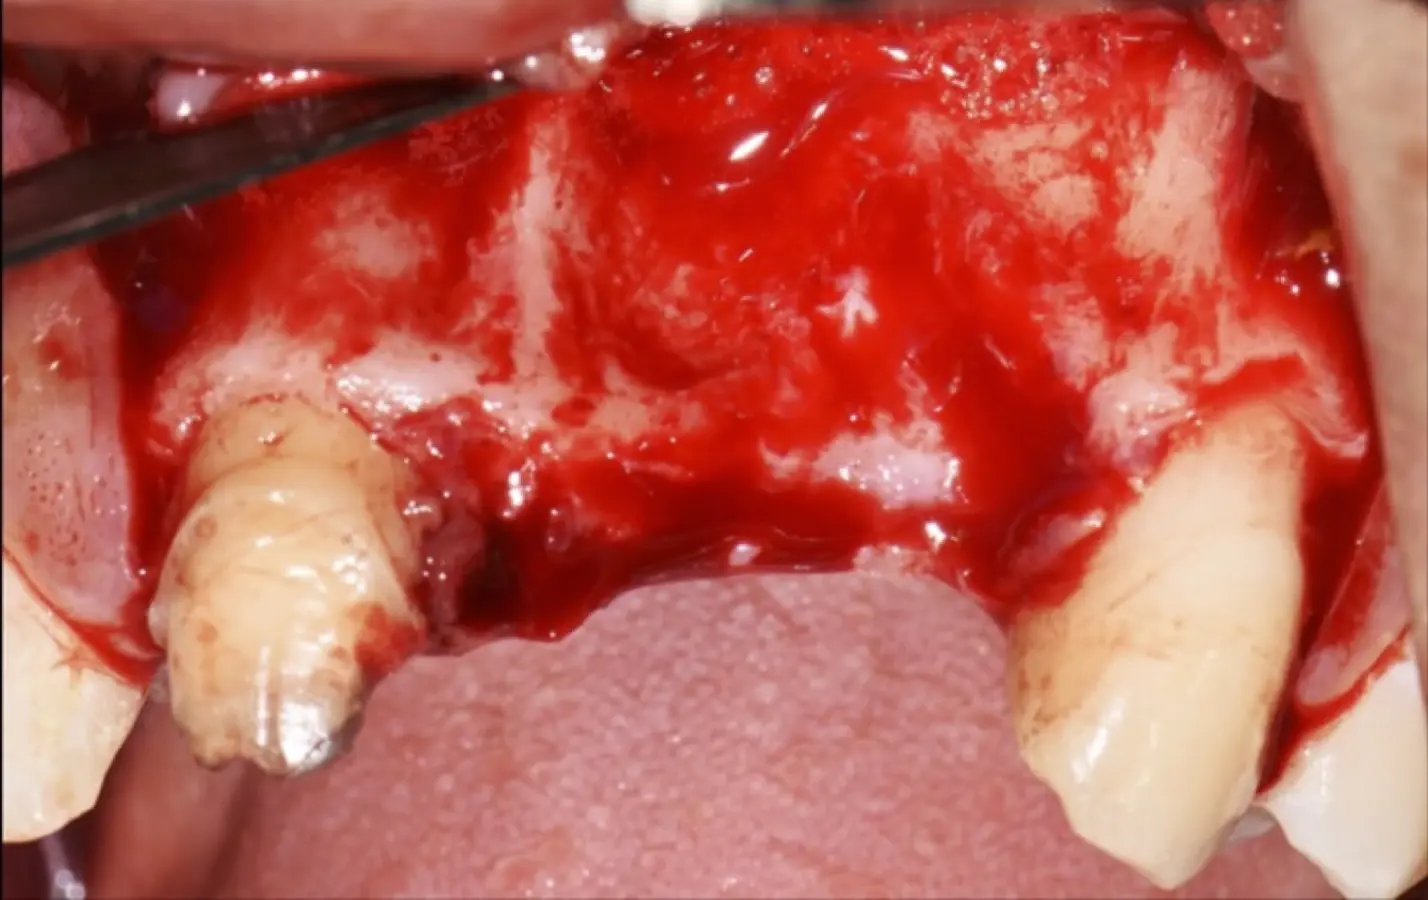

En las imágenes superiores se aprecia una reconstrucción de reborde con injertos en bloque previo a la planificación de implantes; en las imágenes inferiores, se observa la deficiencia vertical del reborde óseo y el tratamiento realizado con el piezoeléctrico.

Paciente de sexo femenino de 36 años de edad, llega a la consulta por presentar una restauración protésica inadecuada. En el examen clínico se observa una restauración protésica provisional acrílica sobre las piezas 1.1 y 2.2. Adicionalmente, se aprecia recesión gingival a nivel de la pieza 2.2 y deficiencia horizontal severa de reborde a nivel de la zona edéntula correspondiente a la pieza 2.1. En la evaluación tomográfica se observa ausencia total de tabla ósea vestibular en la pieza 2.2, y se corrobora el déficit en la zona edéntula de la pieza 2.1, para lo cual se indica una reconstrucción de estructuras óseas con hueso en bloque de origen bovino y posteriormente la colocación de implantes dentales.

Figura 35. Decolado a espesor total sobrepasando la línea mucogingival (a, b).

Figura 36. Defecto óseo y severa reabsorción ósea horizontal: vista clínica (a) y corte tomográfico (b).